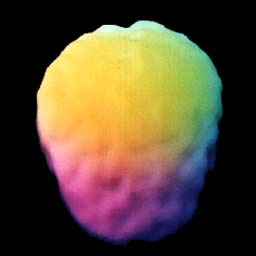

Este é o seu cérebro. ![]() Vista em 3D do topo de um cérebro adulto saudável |

O cérebro normal é liso, simétrico e cheio. |